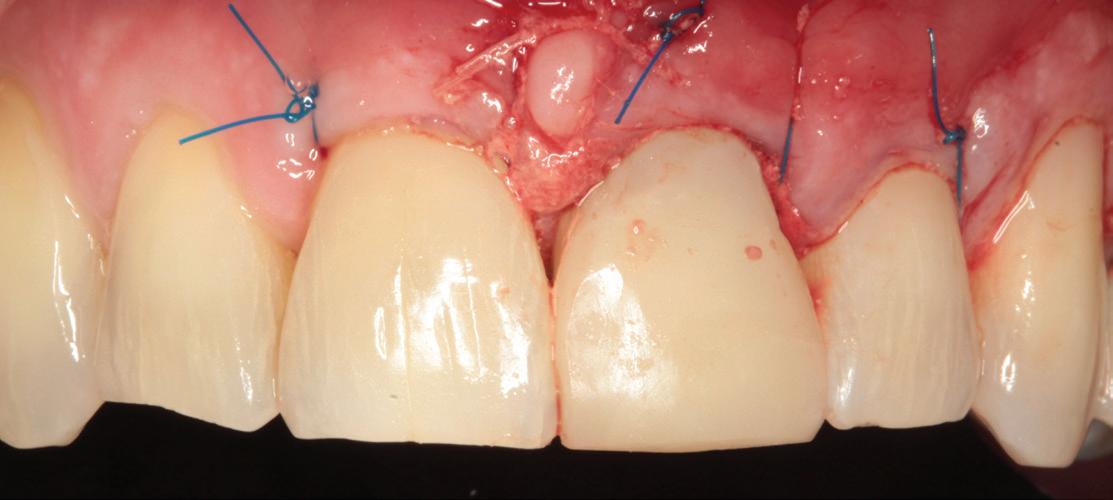

SITE AUGMENTATION Reconstituirea țesutului moale periimplantar și papilar în zona estetică

RECONSTITUIREA țesuturilor moi periimplantare. Scopul acestui raport de caz este de a demonstra procedurile chirurgicale utilizate pentru corectarea unui defect al țesuturilor moi periimplantare folosind țesutul moale interdentar în combinație cu tuberozitatea ca locație donatoare de țesut conjunctiv, utilizând o abordare prin tunelizare într-o zonă estetică.